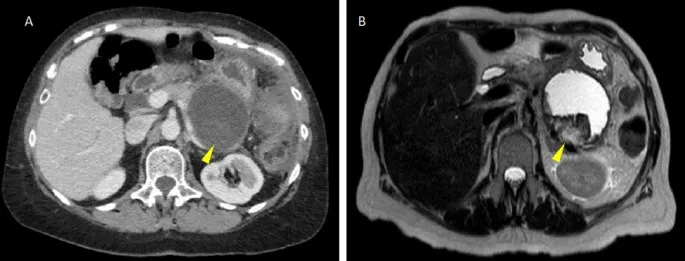

- Imaging (CECT): Shows non-enhancing pancreatic parenchyma with heterogeneous fluid/debris. Gas bubbles imply infection.

- Contrast-enhanced CT (CECT) is the imaging modality of choice to differentiate fluid from necrosis.